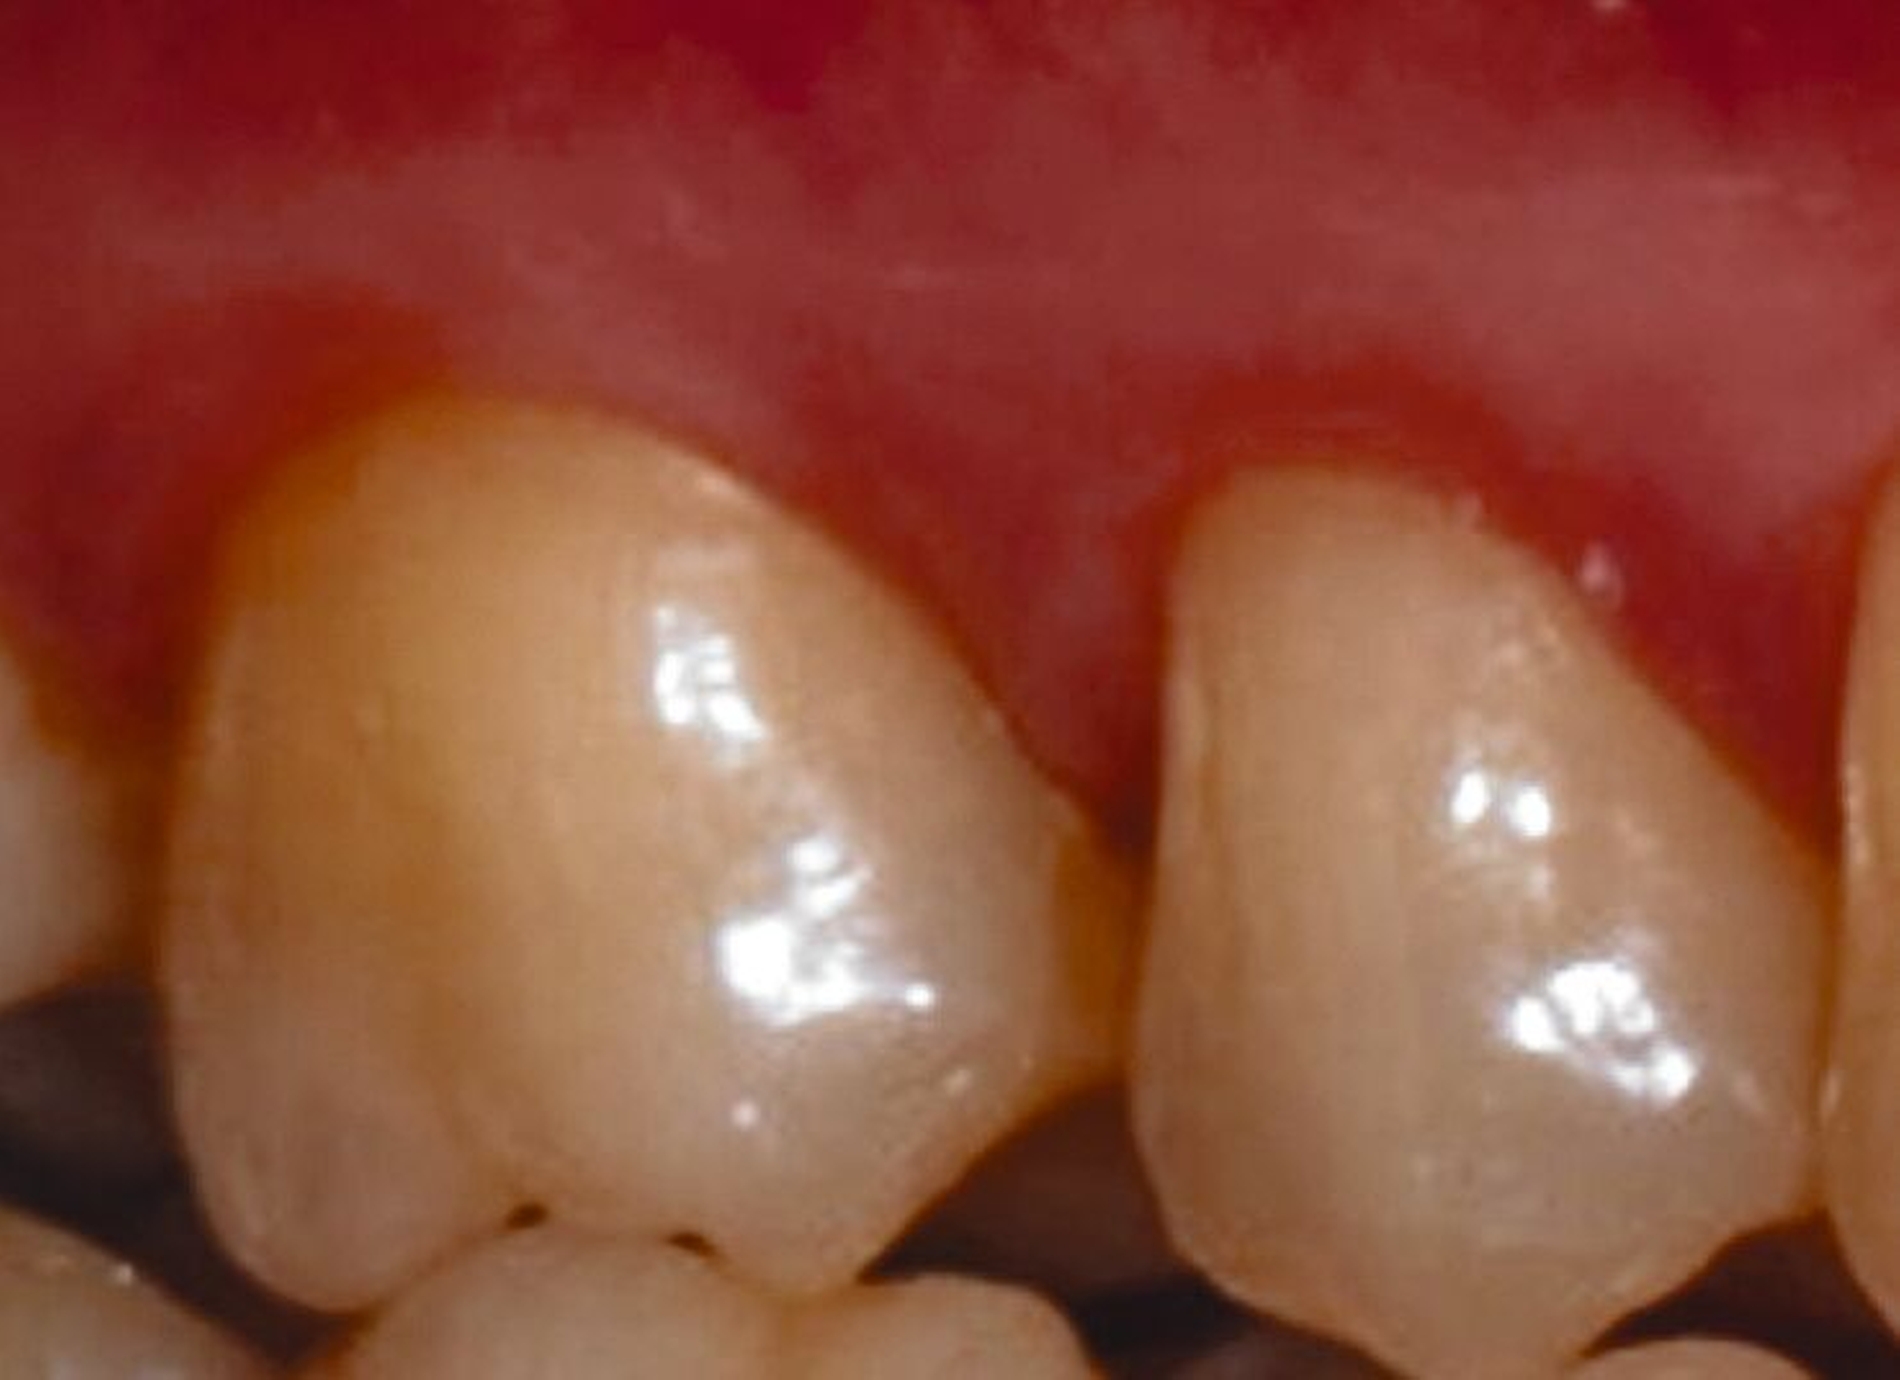

Systemische Faktoren, die den Erfolg regenerativer Maßnahmen beeinflussen können, sind beispielsweise ein unkontrollierter Diabetes oder eine eingeschränkte Immunabwehr. Verhaltensfaktoren wie Rauchen, unzureichende Mundhygiene und mangelnde Adhärenz müssen ebenfalls bei der Fallauswahl berücksichtigt werden. Zu den anatomischen beziehungsweise Defektfaktoren, die sich einigen Studien zufolge und nach Expertenkonsens negativ auf die Erfolgsaussichten einer regenerativen Furkationstherapie auswirken können, werden gezählt: ein erschwerter Zugang zum Operationsbereich, ein approximales Knochenniveau, das sich auf derselben Höhe oder sogar apikal des Furkationsdaches befindet, ein kurzer Wurzelstamm, ein enger Abstand zwischen den Wurzeln mit erschwerter Instrumentierung, eine deutlich erhöhte Zahnbeweglichkeit, ein dünner gingivaler Phänotyp, wenig keratinisiertes Gewebe, die Nähe eines Restaurationsrandes zum Furkationseingang und das Vorliegen einer gingivalen Rezession im Furkationsbereich.

Ein adäquater Zugang zum Operationsbereich und auch für die zukünftigen Mundhygienemaßnahmen ist äußerst wichtig. Molaren mit Grad-II-Furkationsdefekten (mandibulär und bukkal maxillär) sind Kandidaten, die für ein regeneratives Verfahren infrage kommen. Basierend auf der verfügbaren Evidenz sind interdentale Grad-II-Furkationsdefekte an Oberkiefermolaren deutlich weniger geeignet, höchstwahrscheinlich aufgrund des eingeschränkten Zugangs. Weitere lokale Charakteristika können Auswirkungen auf die Ergebnisse der regenerativen Furkationschirurgie haben. Zum Beispiel können ein dickerer Phänotyp und das Fehlen einer Weichgeweberezession die Heilung nach GTR-Verfahren positiv beeinflussen. Günstigere Ergebnisse sind an Stellen zu erwarten, an denen das verbleibende approximale Knochenniveau koronal zum Eingang beziehungsweise zum Dach des Furkationsdefekts liegt, verglichen mit solchen, bei denen das approximale Knochenniveau auf der Höhe oder apikal des Furkationseingangs liegt. Ein enger interradikulärer Abstand kann eine gründliche Defektinstrumentierung beeinträchtigen. Das Vorhandensein einer Wurzelkanalfüllung ist nicht per se eine Kontraindikation für die Furkationsregeneration – vorausgesetzt, es gibt keine Anzeichen für apikale pathologische Veränderungen.